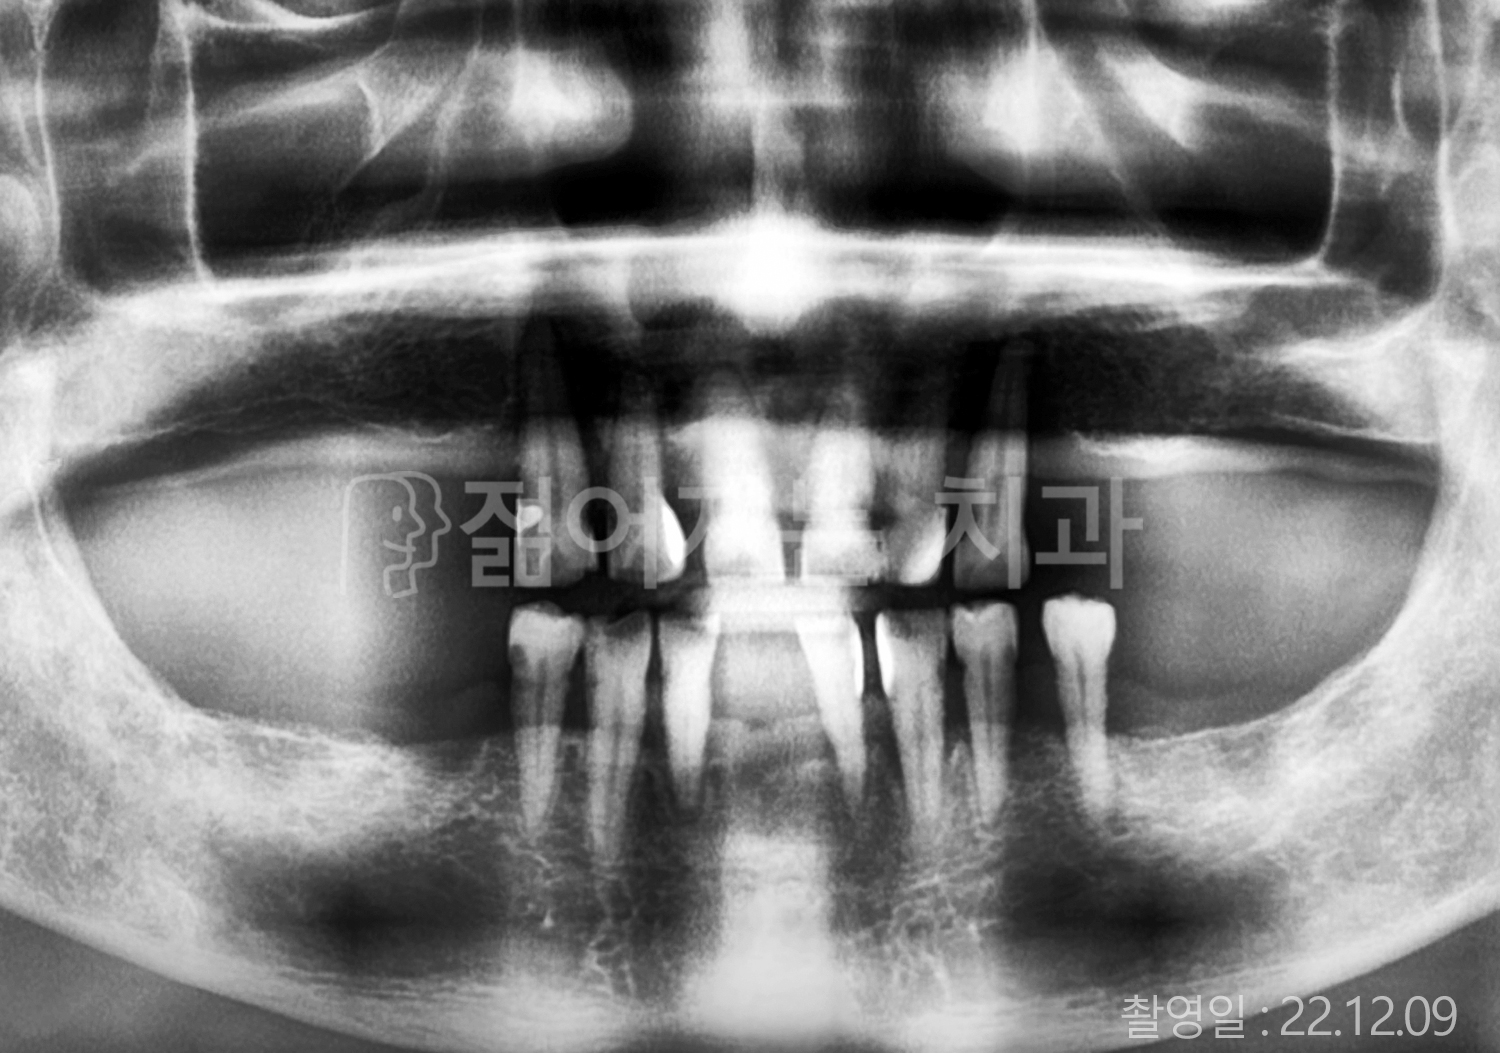

• 70대 고혈압, 당뇨 전체치아 10개 이상 임플란트

• 50대 고혈압, 당뇨 전체치아 10개 이상 임플란트

• 60대 고혈압, 당뇨 전체치아 10개 이상 임플란트

• 50대 전체치아 10개 이상 임플란트

• 70대 당뇨 전체치아 10개 이상 임플란트

• 80대 전체치아 10개 이상 임플란트

• 40대 전체치아 10개 이상 임플란트

• 60대 고협압, 고지혈증 전체치아 10개 이상 임플란트

• 60대 전체치아 10개 이상 임플란트